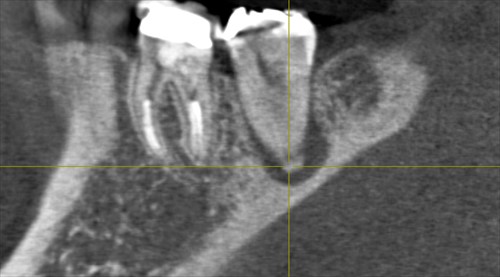

本日はエンド、ペリオ(重症のむし歯で神経が死に歯周病を併発した)患者さまの型とりの日でした。下記のように根の先に膿が出来てしまいそれが歯周ポケットと交通しています。ポケットは9mm。割れてはいないようでした。

CTでこのように精密に診断することにより的確な治療方法がお話でき納得されていました。

根管治療→歯周病治療→再検査→かぶせ物の計画です。